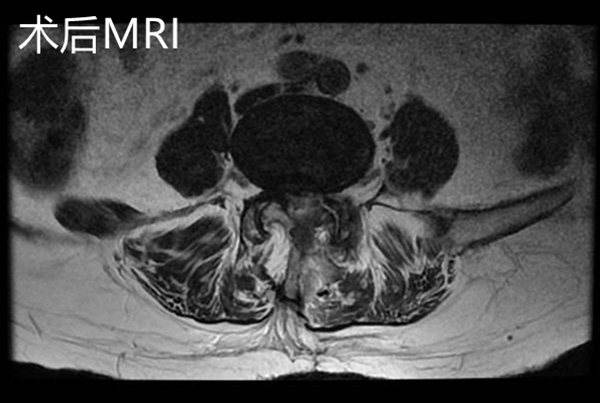

在完善術前檢查,排除手術禁忌,充分做好術前準備后,該手術由微創手術經驗豐富的羅同青副主任醫師主刀。因患者高齡,該手術在局部麻醉+靜脈麻醉下進行,術中麻醉醫師一刻也不敢放松,緊盯監視器屏幕,不斷監測病人的各項生命體征,及時調整藥量,認真配合手術醫生,保證手術順利進行。經過約2小時,成功解除了患者的腰椎管狹窄及神經根壓迫,術中出血約10ml,手術順利,沒有出現神經損傷等并發癥。

手術后復查腰椎MRI顯示:相應的椎管狹窄及神經根壓迫已解除,手術后第2天邱奶奶便可下地行走,腰痛及左下肢疼痛緩解,復查腰椎磁共振見L4/5左側狹窄已完全解除。手術后第4天,患者順利出院,沒有出現任何手術并發癥。